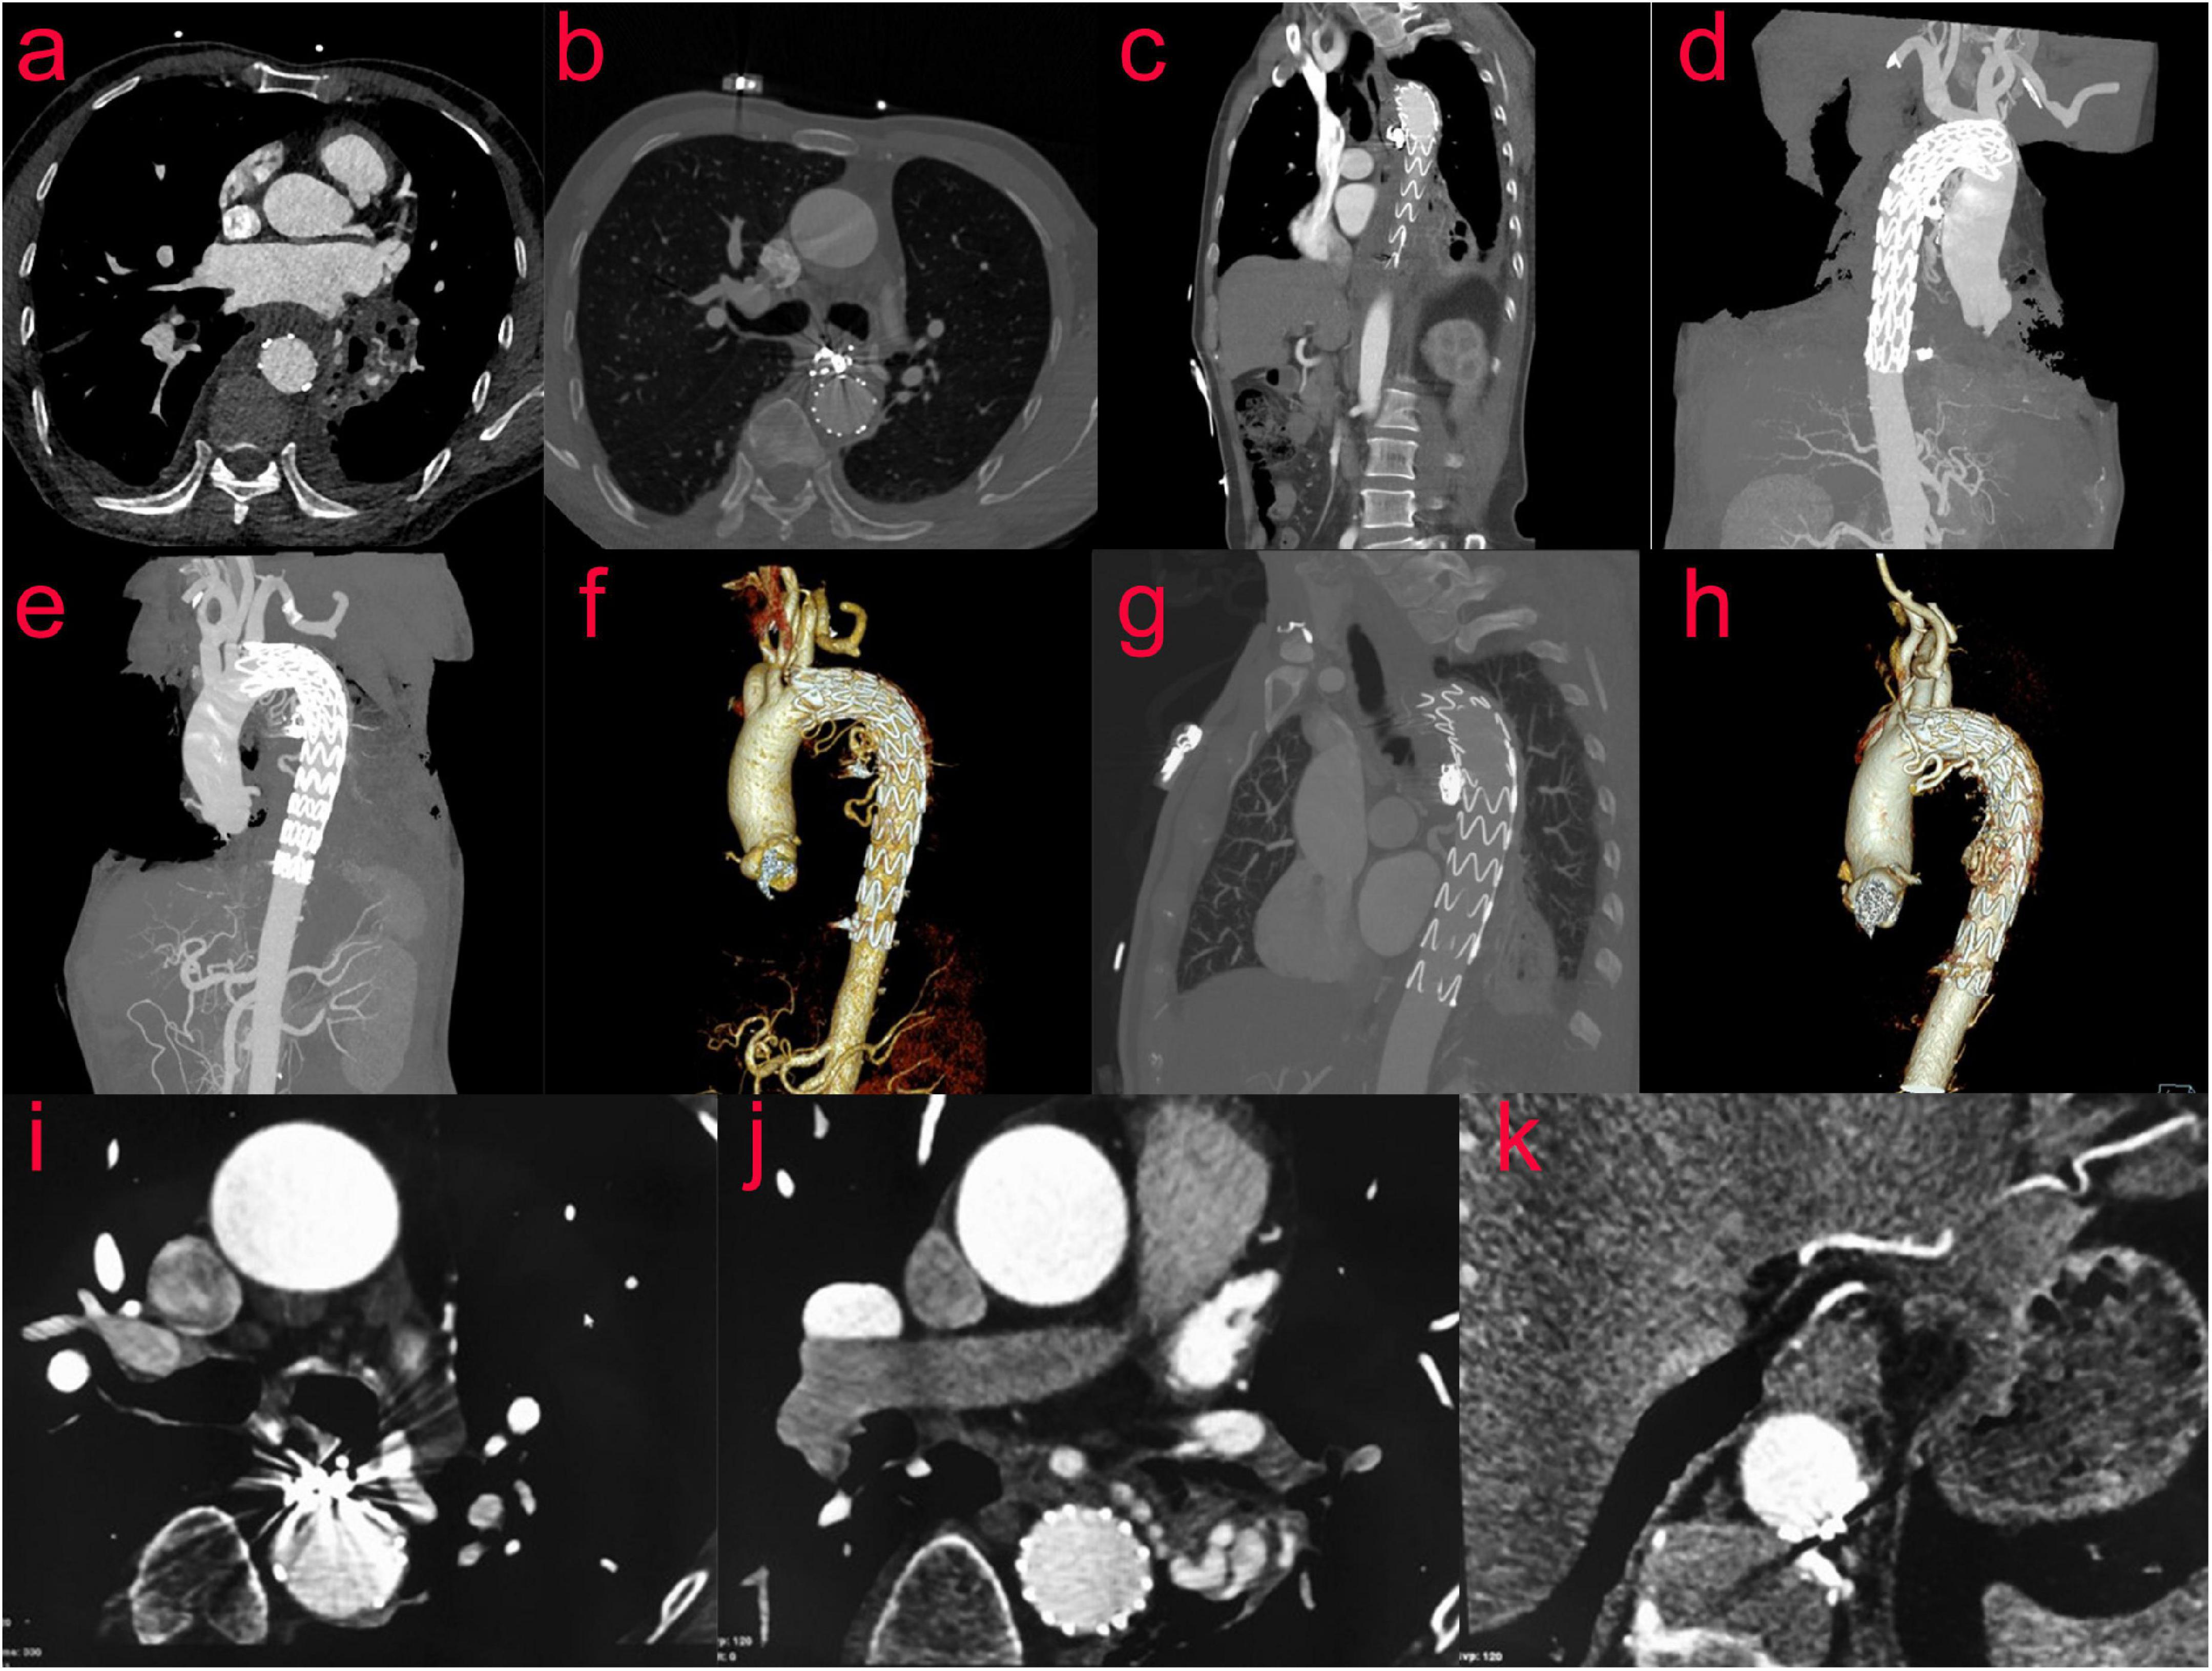

CTA of thoracic aorta was reexamined 10 days after operation: after stenting of aortic arch and descending aorta, the shape and position of metal stents were good. It adhered to the wall well, and there was no displacement or internal leakage. The mediastinal hematoma was partially absorbed (Figures 4a–f). A CT scan performed after 2 months showed no endoleak, no stent migration and the mediastinal hematoma was further absorbed. (Figures 4g,h). Nine months after the operation, the mediastinal hematoma was almost completely absorbed (Figures 4i–k).

FIGURE 4

(Case two) CTA of the thoracic aorta was reexamined 10 days after the operation (a–f). After stenting of the aortic arch and descending aorta, the shape and position of the metal stents were evaluated to be good. It adhered to the wall well, and there was no displacement or internal leakage. The mediastinal hematoma was partially absorbed. After 2 months, the reexamination of the thoracic aorta by CTA showed that the mediastinal hematoma was further absorbed, and the stent was in good shape (g,h). Nine months after the operation, the review of CT showed that the mediastinal hematoma was almost completely absorbed (i–k).